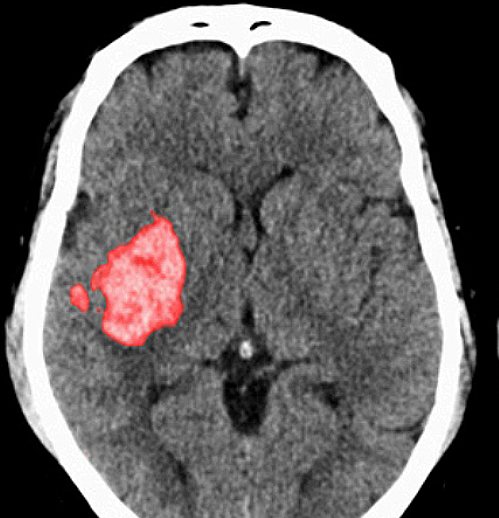

증상이 나타나면 검사를 통해 정확한 진단이 필요합니다. 보통 MRI, 경동맥 초음파 등을 통해 증상을 확인합니다. 뇌의 단층을 촬영하고 뇌혈류 검사와 뇌혈관조영술 등 여러 방법을 통해 질환을 확인합니다.